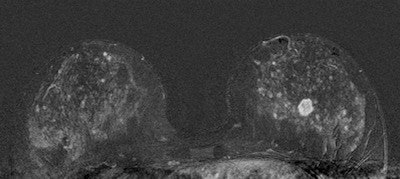

| 45-year-old asyptomatic woman with family history of breast cancer underwent mammography and MRI for screening. Full field digital mammogram is normal. Coned down view was done after MRI. MRI depicts a well circumscribed tumor with fast and early enhancement, strong wash out, and peripheral (rim) enhancement. This is high grade invasive cancer (basal-like) without calcifications; even coned down view is unremarkable. All images courtesy of Dr. Christiane Kuhl |